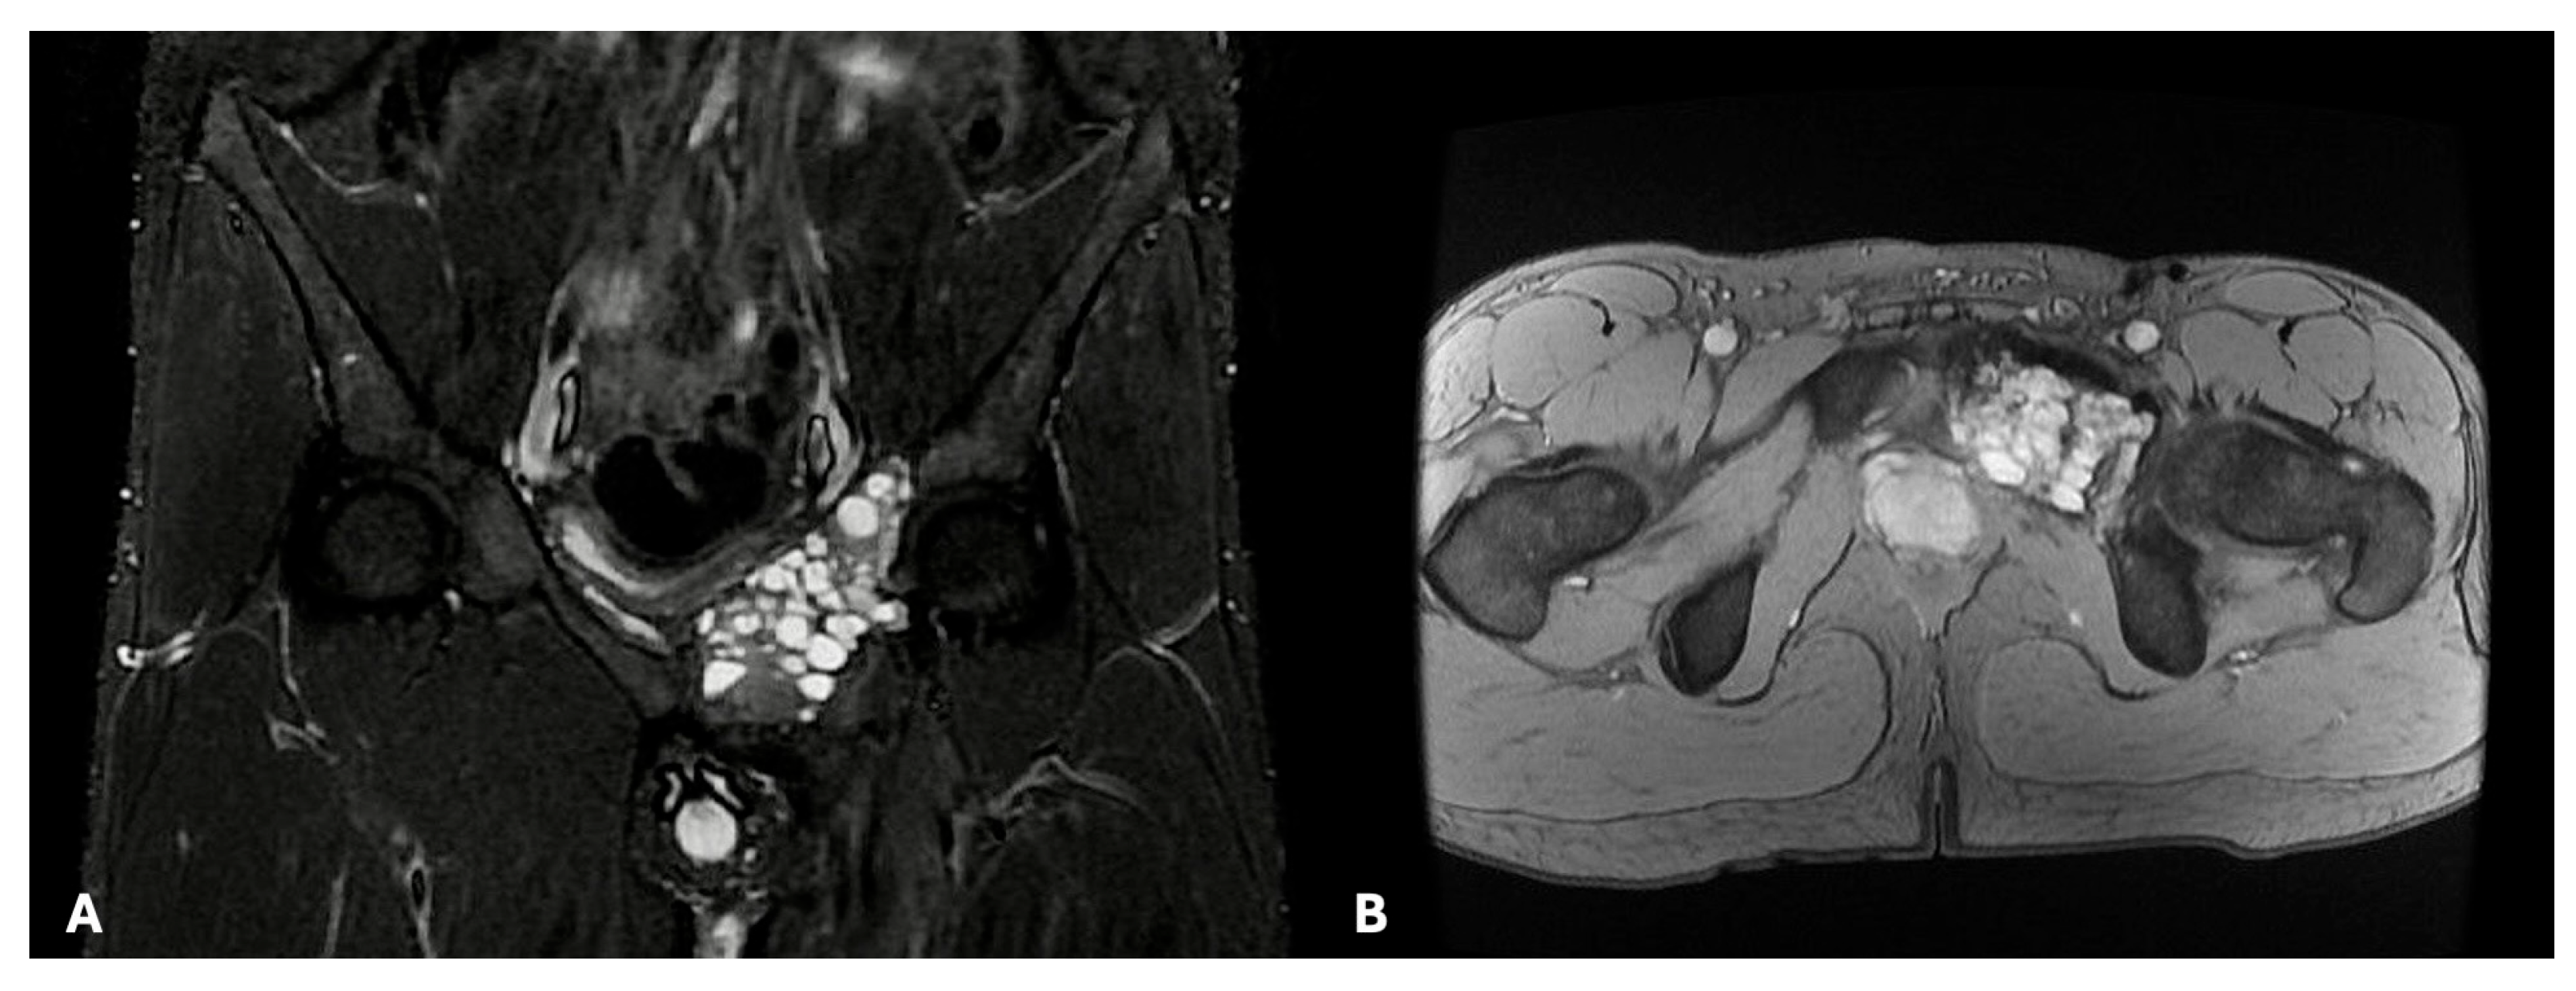

- Ma, X.N.; Qiang, S.; Liu, T.Y.; Cao, M.Y.; Lv, S.C. Massive rare desmoplastic fibroma of the ilium and ischium in a young adult: A case report. Medicine 2017, 96, e8962. [Google Scholar] [CrossRef] [PubMed]